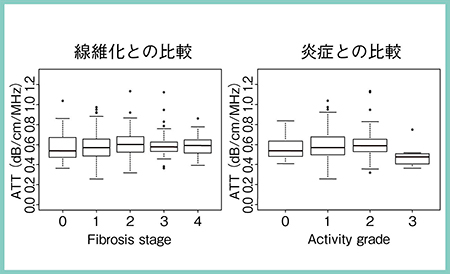

通常,エコービームは深部ほど減衰が大きくなることから,日立はSWMと連動して超音波減衰(ATT)を計測する機能を開発し,ARIETTA 850に搭載した。われわれは,ATTを用いて慢性肝疾患353名の減衰と脂肪化の程度の相関を検討した。まず,各症例の病理組織の脂肪化面積を自動算出して定量し,病理学的な脂肪化の程度(steatosis grade)と比較したところ,明らかな正の相関が見られた。また,ATTとsteatosis gradeとの比較でも同様であり(図4),ATTを測定することで肝の脂肪化の程度を非侵襲的に予測可能であった。一方,ATTと,線維化ステージおよび炎症を比較すると,いずれもATTにはまったく変化が見られなかった(図5)。ATTは純粋に脂肪化の程度を反映して定量化できることから,今後,ATTの測定は臨床でも普及すると考えられる。

図5 ATTと線維化ステージおよび炎症との比較6)